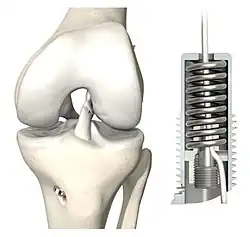

Kreuzbanderhaltende Operationsmethoden sind noch junge Verfahren, die ohne ersetzendes Sehnen-Transplantat auskommen.[256] Sie können nur innerhalb der ersten drei Wochen nach einem Kreuzbandriss angewendet werden. Diese zeitliche Begrenzung hat ihre Ursache darin, dass vor allem die vorhandene Heilungskapazität eines Kreuzbandes genutzt werden soll, welche ziemlich schnell nachlässt.[98][97] Der angestrebte natürliche Vernarbungsprozess[257] des Kreuzbandes wird durch eine biomechanische Stabilisation des Kniegelenkes, einer anatomischen Reposition der verletzten Bandstruktur sowie einer Mikrofrakturierung (Healing Response) erreicht.

Aktuell werden zwei Verfahren angewendet: ein erster Behandlungsansatz ist dynamisch (Federmechanismus) basiert, der zweite setzt auf eine starre, unflexible Stabilisation des Kniegelenks. Bei der dynamischen Methode wird das Kreuzband mit bioresorbierbaren Nähten reponiert und das Knie mit einem dünnen, sehr reißfesten Implantat-Faden stabilisiert. Die flexible Dynamik des Federelementes im Schienbein sorgt dafür, dass bei allen Beuge- und Streckbewegungen das heilende Band entlastet wird. Bei der unelastischen Methode werden ein starr fixiertes Polyethylen-Band zur Kniestabilisierung sowie nicht-resorbierbare Nähte und kleine Anker verwendet, um das abgerissene Kreuzband an die originäre Abrissstelle zurückzuführen, bis es wieder angewachsen ist.[258]